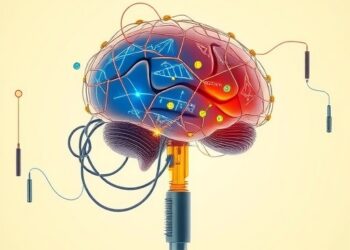

University of Michigan Achieves First Human Implantation of Paradromics Wireless Brain-Computer Interface to Restore Communication

In a groundbreaking advancement that merges neurosurgery and cutting-edge biomedical engineering, University of Michigan Health has achieved the first-ever human...

Dual-Mode Wireless Microsystem Enables Real-Time Monitoring of Dopamine and Neural Spike Activity During Dexmedetomidine Administration

In a groundbreaking advancement in neuroscience technology, researchers from the Aerospace Information Research Institute at the Chinese Academy of Sciences...